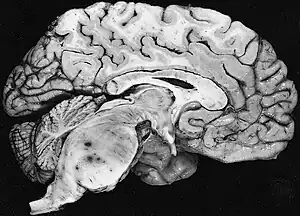

| Diffuse fibrillary astrocytomas arising in the brain stem favor the pons: The tumor here produces the classic hypertrophy of the affected region. | |